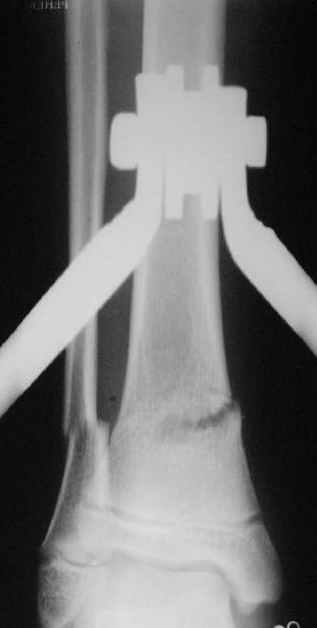

Уважаемые коллеги!Поступила пациентка 40лет, псевдоартроз Н/3 большеберцовой кости, оперирована 1,5-а года назад по поводу перелома ПИЛОНА в Австрии, травма горнолыжная.

после остеосиннтеза |  05.07.04 |  12.04.05 | Пластина удалена через 4-е месяца (миграция винтов), полимерная повязка на 2-а мес. Беспокоит деформация голени,укорочение 1-1,5см, боли незначительные, движения в г/стопном суставе в полном объёме, ходит с полной нагрузкой на ногу, подвижность в переломе не определяется. Одномоментное исправление деформации, костная пластика (chronOS)+ пластина? Аппаратная коррекция, затем пластина? Аппарат? Прошу Ваших советов. С Уважением А.Миронов